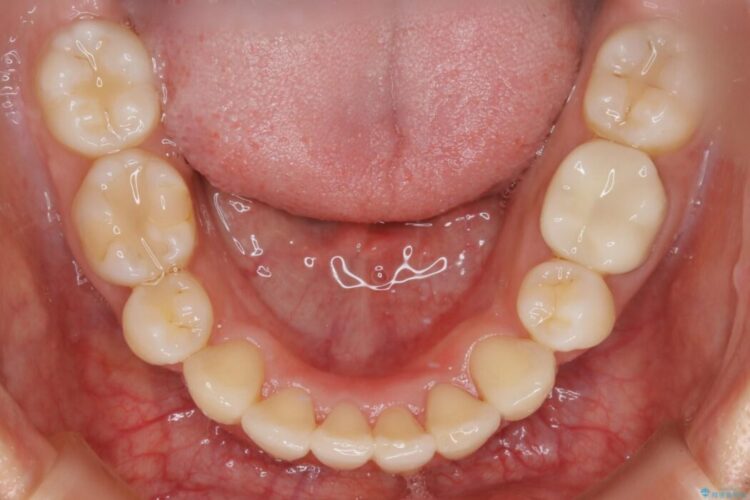

左右の奥歯が前方に寄っていることにより八重歯の発生や重度の叢生に繋がっていました。

ですが詳しく検査をしたところ、左右の奥歯の前後位置に関してはズレが少ない状態でした。

加えて患者様の顎の大きさに対する歯の数が多いことが叢生の原因になっていることから、抜歯した上で歯列を整えるほうが最終的な仕上がりとして良い結果になると判断しました。

まず噛み合わせに問題が少ない奥歯の位置を極力変えないように上下左右4番目の歯を抜歯することで歯列矯正のためのスペースを確保し、空いた隙間で前歯の凹凸をきれいに並べていくこととしました。